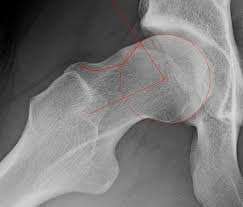

Femoroacetabular impingement (FAI) is a condition that occurs when abnormal contact between the bones of your hip joint leads to pain, stiffness, or limited range of motion. In a healthy hip, the ball (femoral head) moves smoothly within the socket (acetabulum). With FAI, the shape of either the ball or socket or, both is altered, causing the bones to rub against each other during movement. Over time, this repeated contact can damage the cartilage and labrum, increasing the risk of hip osteoarthritis if left untreated. FAI often affects young and active individuals, including athletes, but it can also occur in people with no history of sports participation. If you’re experiencing hip or groin pain, particularly when sitting for long periods or during hip flexion movements (such as squatting or twisting), a thorough orthopaedic assessment can help determine whether FAI is the cause.

Femoroacetabular impingement (FAI), commonly referred to as hip impingement, is a condition where abnormal contact occurs between the ball (femoral head) and socket (acetabulum) of the hip joint. This contact can damage the cartilage and labrum over time, leading to pain, stiffness, and reduced movement.

There are two main types of FAI:

Over time, untreated FAI may increase the risk of developing hip labral tears or early hip osteoarthritis.